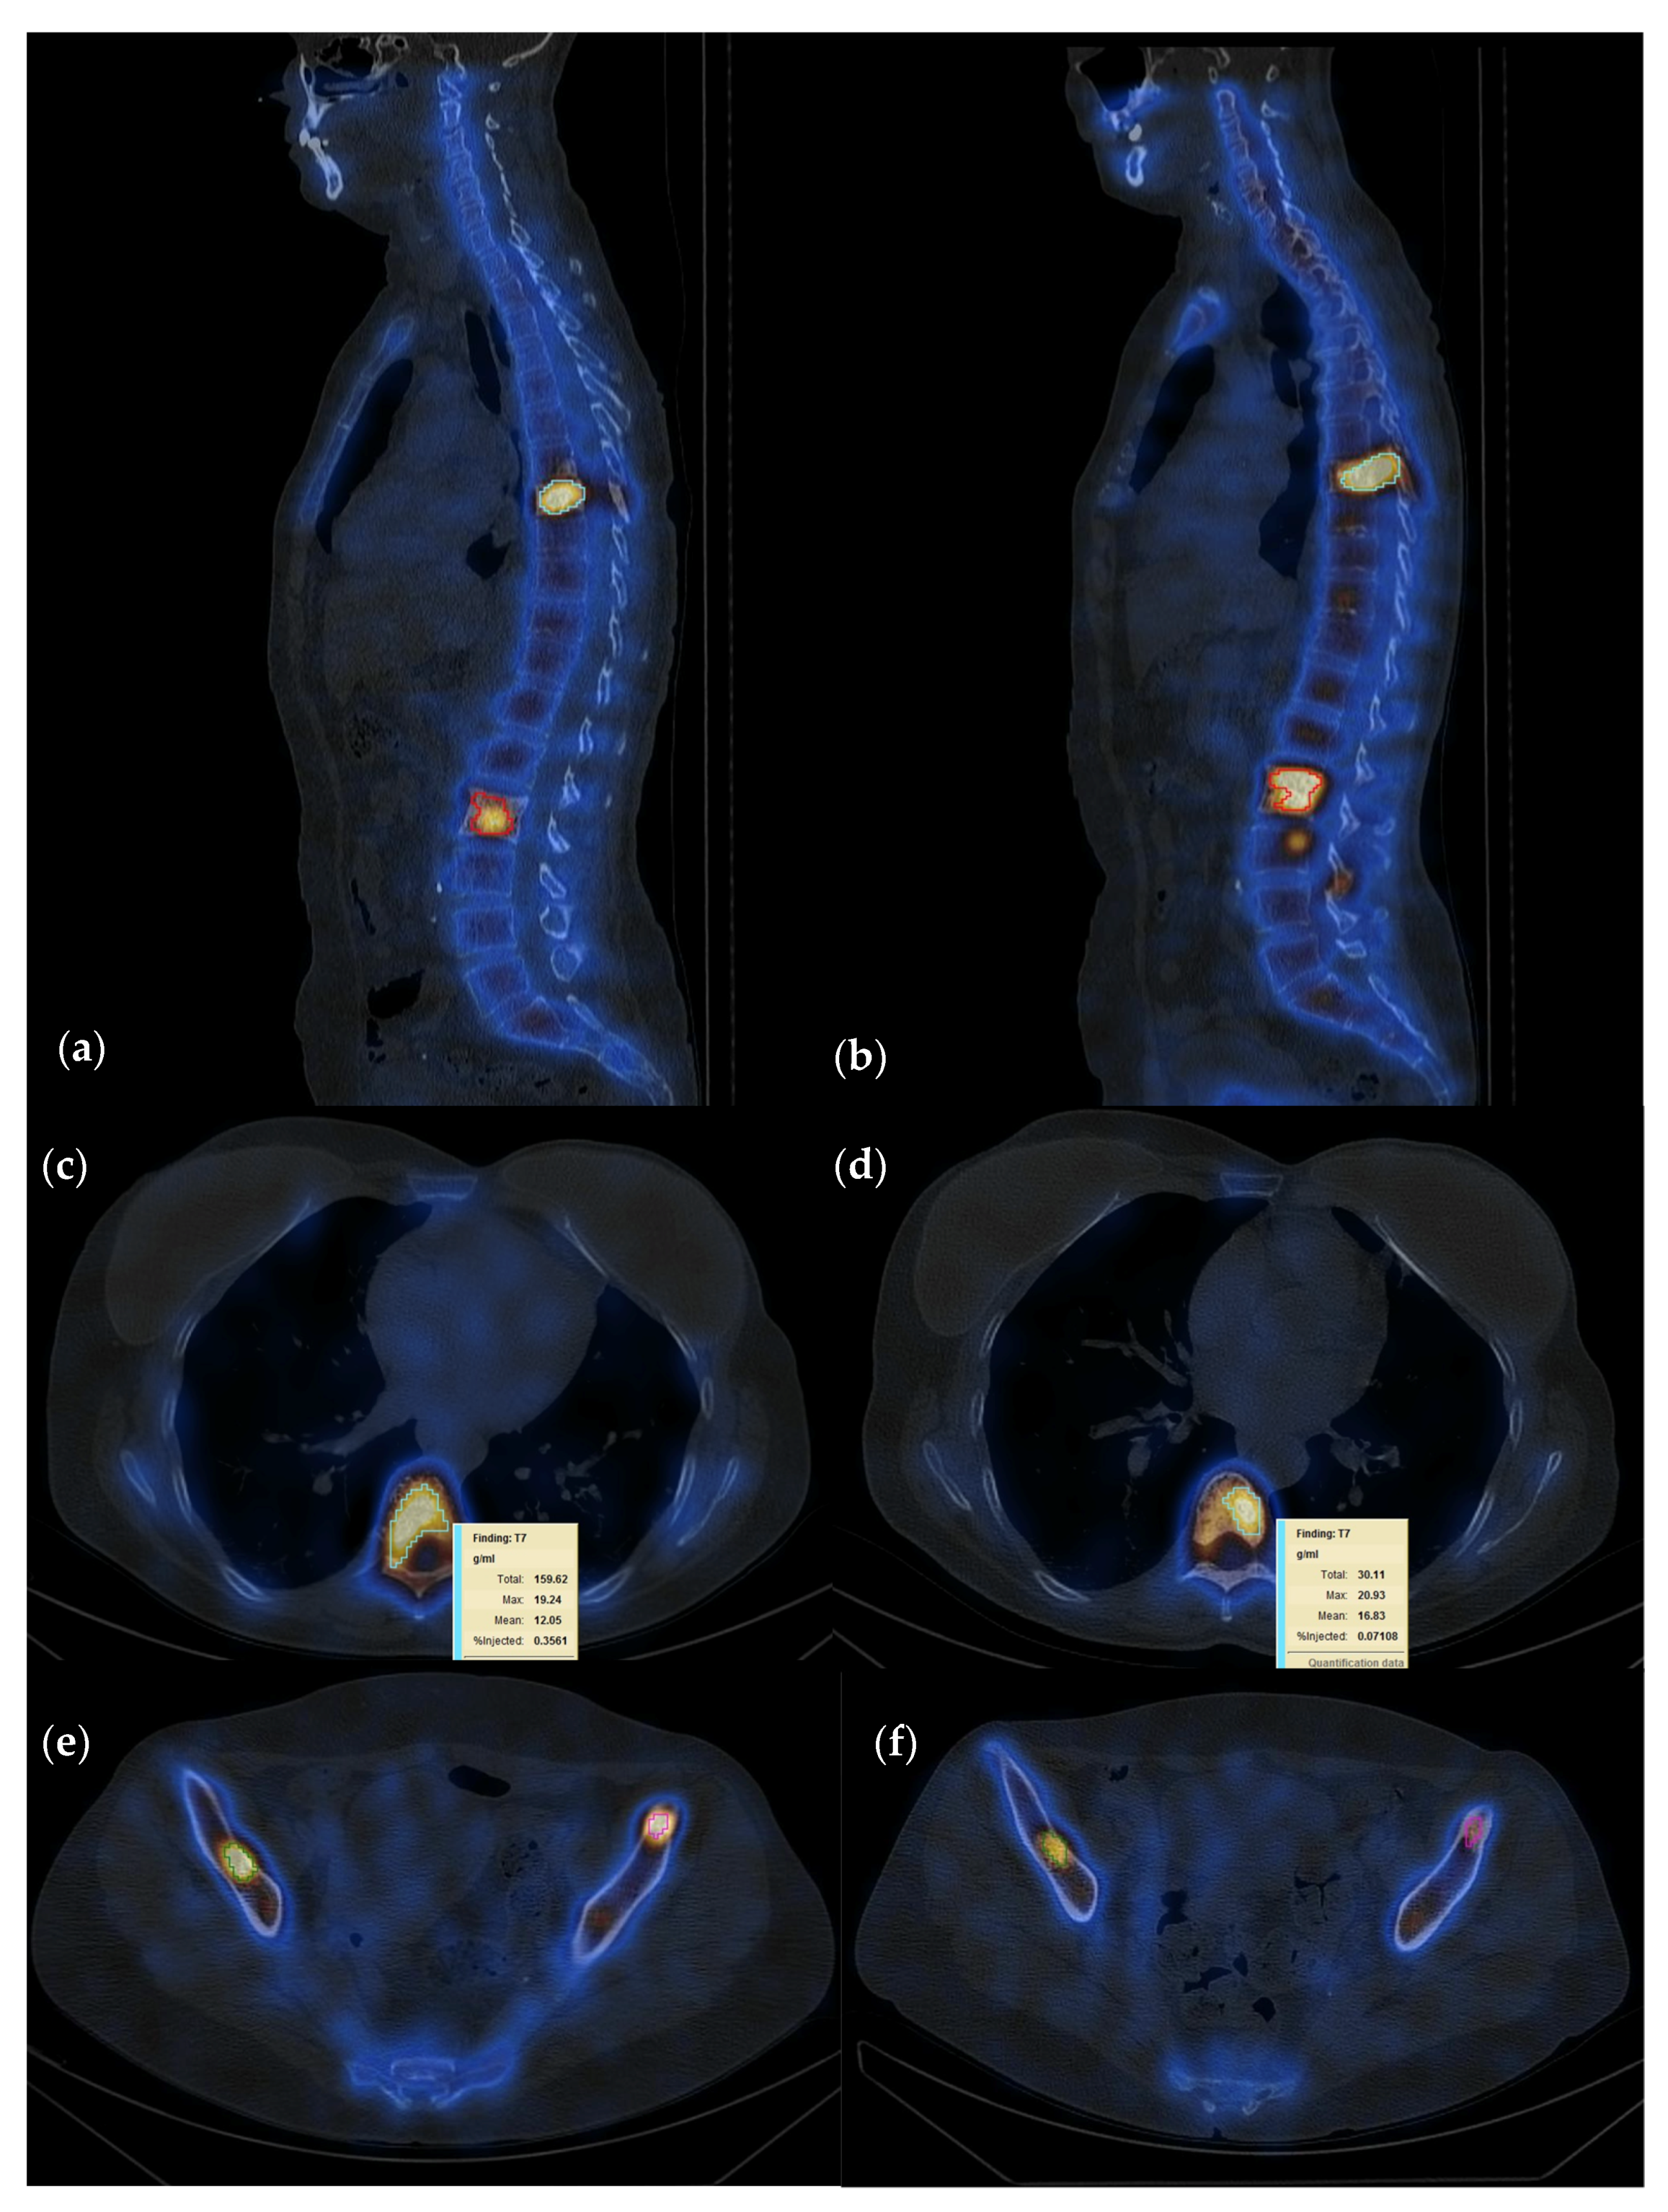

3.4. Interpretation of Quantitative SPECT-CT

| Region | No. of Lesions | Percentage |

|---|---|---|

| Ribs | 26 | 10.44% |

| Thoracic vertebrae (T) | 67 | 26.90% |

| Lumbar vertebrae (L) | 55 | 22.08% |

| Pelvic bones (P) | 60 | 24.09% |

| Other bone sites(O) | 41 | 16.46% |